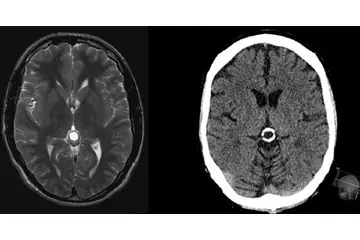

Beyin Dokusunun Sağlık Üzerindeki Etkileri Beyin dokusunun sağlıklı bir şekilde işlev görmesi, genel sağlık üzerinde büyük etkiye sahiptir. Beyin dokusundaki hasar veya bozulmalar, birçok nörolojik hastalığın temelini oluşturur. Öne çıkan sağlık sorunları arasında: